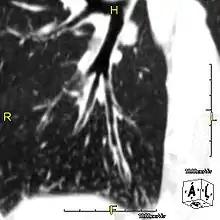

Sagittal CT image showing "tree in bud" appearance of mucous impaction in distal small airways related to primary ciliary dyskinesia

CT image showing dilated and thickened medium-sized airways (bronchiectasis) in a patient with Kartagener syndrome

Oblique sagittal CT image showing lower lobe cylindrical bronchiectasis in the same patient